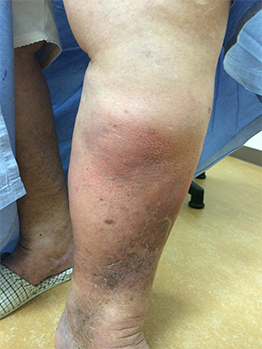

下肢静脈瘤を長期間放置すると、うっ滞性皮膚炎を起こし、しだいに皮膚や脂肪織が肥厚・線維化を起こし硬くなってきます。脂肪皮膚硬化症とは、うっ滞性皮膚炎が重症化して、皮下脂肪が炎症によって硬くなってしまったものです。赤く腫れて皮膚と皮下脂肪がカチカチに硬くなり痛みを伴います。これをさらに放置しておくと、皮膚に穴があく潰瘍になります。一度潰瘍になってしまうと、治るまでに数ヶ月かかってしまいます。

症例写真:脂肪皮膚硬化症1、皮膚潰瘍1−2

脂肪皮膚硬化症1